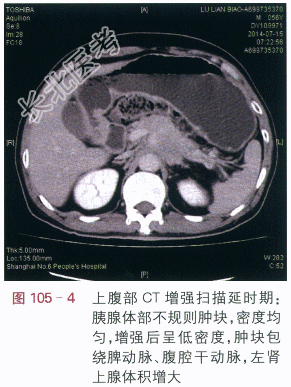

读片分析:上腹部CT平扫显示胰腺体部增大,密度均匀,尾部萎缩,胰腺周边模糊(见图105-1),增强扫描动脉期:胰腺体部不规则肿块,增强后动脉期呈低密度,肿块边缘不清,肿块包绕脾动脉、腹腔干动脉(见图105-2);门脉期:胰腺体部不规则低密度肿块,肿块包绕脾静脉(见图105-3)。延时期肿块密度呈低密度,肿块包绕腹腔血管、并向周边侵犯,左肾上腺体积增大(见图105-4)。